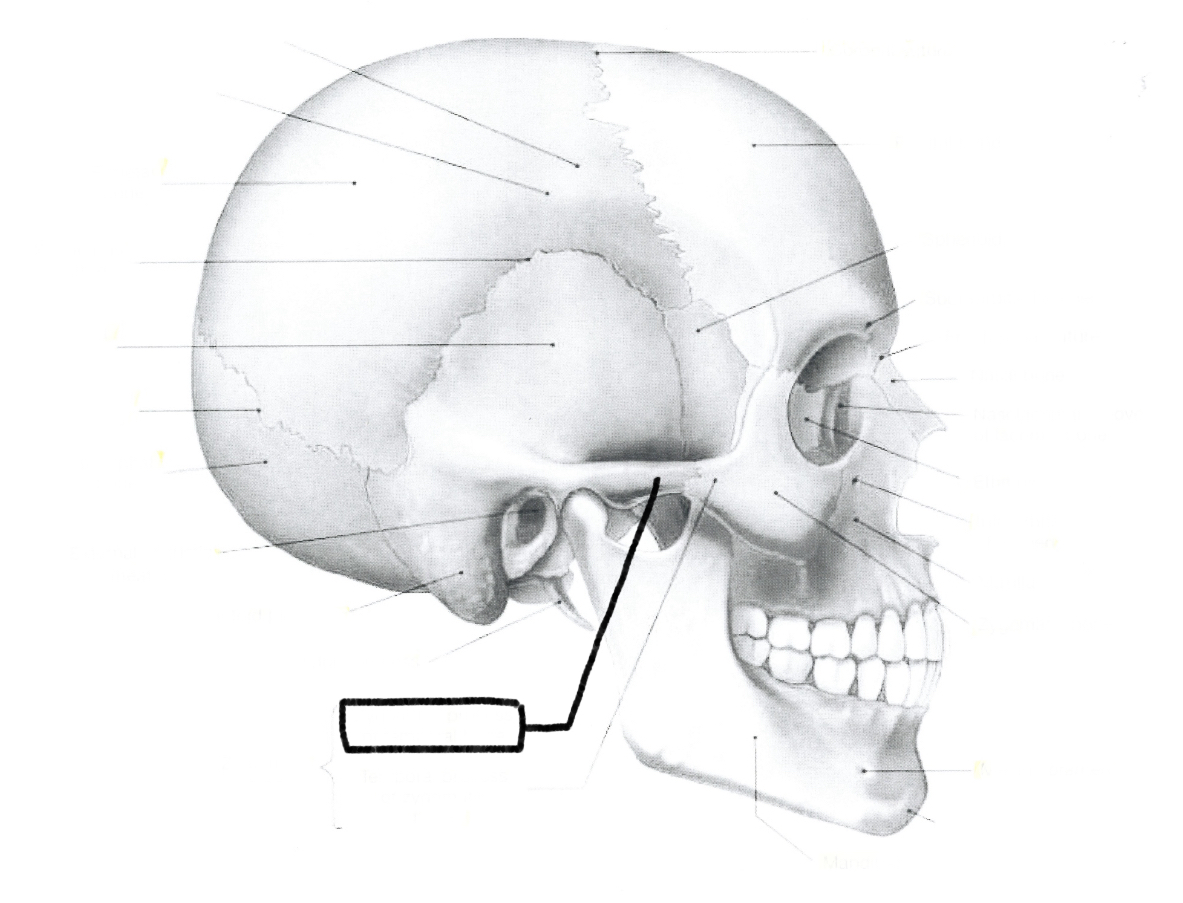

What is this?

Zygomatic process of temporal bone